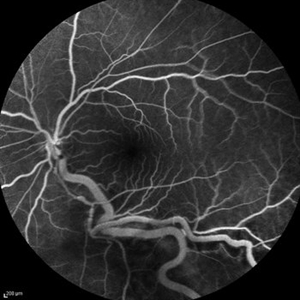

Behcet's Disease Behcet's DiseaseMar 13 2013 by Hamid Ahmadieh, MD Early phase FA of the right eye of a 23-year-old man with retinal vasculitis and branch retinal vein occlusion (BRVO) due to Behcet's disease . Photographer: Solmaz Shahmohammad, Negah Eye Center, Tehran Imaging device: Heidelberg Spectralis Condition/keywords: branch retinal vein occlusion (BRVO), retinal vasculitis